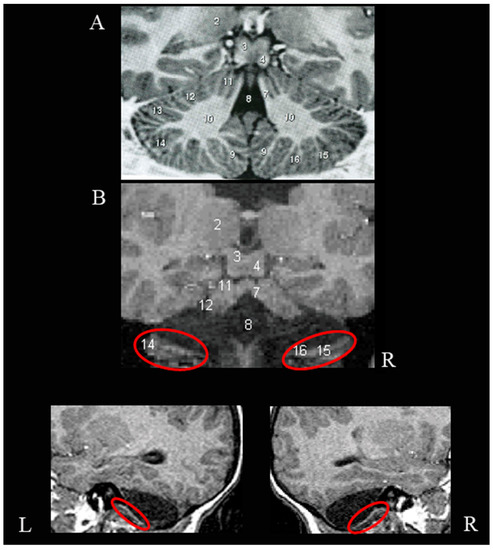

3.1. Neuroradiological Examination